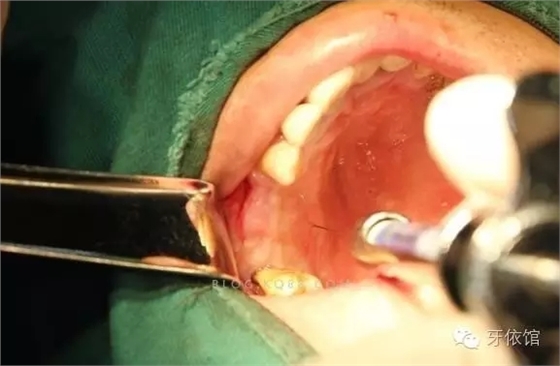

抽2ml生理鹽水,用橡皮塞子塞緊窩洞,速度要稍快一些將生理鹽水推入竇底膜下。

回吸時(shí)液體的量不應(yīng)少于原來的生理鹽水量,如果明顯少于原來的量,考慮是否有膜破裂。